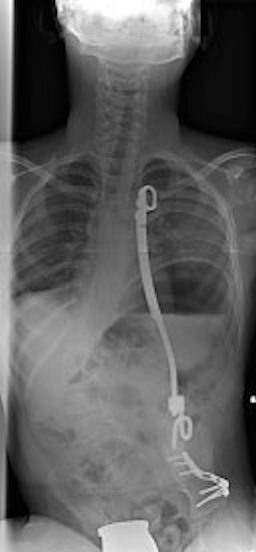

Die nicht selten begleitende Wirbelsäulen-Skoliose muss von kinderorthopädischer Seite aufgerichtet werden, was heute und wenn es rechtzeitig vorgenommen wird, häufig mit der VEPTR (Vertical Expandable Prosthetic Titanium Rib)-Methode über mehrere Jahre vorgenommen wird (Abbildung 3 [Abb. 3]).

Abbildung 3: Hochgradige Skoliose, kinderorthopädische Korrektur mittels Vertical Expandable Prosthetic Titanium Rib – VEPTR